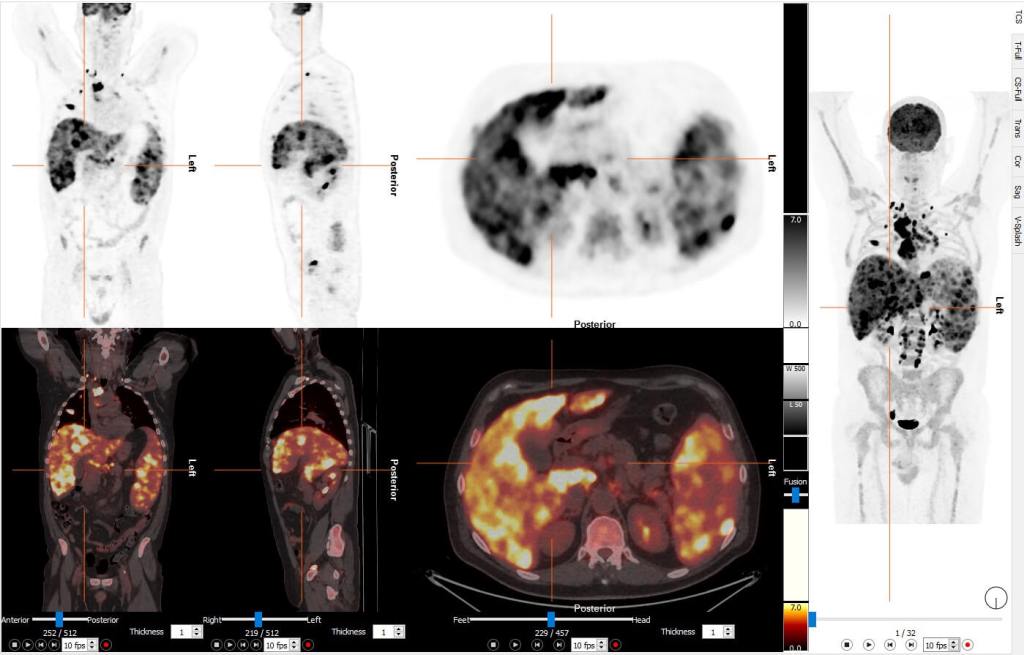

Ahí es donde entra en juego la Tomografía por Emisión de Positrones, más conocida como PET. Esta técnica no se conforma con mirar. Observa la actividad, el metabolismo, el comportamiento real de los órganos. En lugar de una fotografía estática, ofrece una película en movimiento del cuerpo humano. Una forma de detectar problemas antes de que dejen huella.

Todo empieza con la inyección de un radiofármaco, que es una sustancia que contiene un isótopo radiactivo y que se utiliza con fines diagnósticos en medicina nuclear. El más habitual se llama fluor-deoxi-glucosa (FDG), una molécula de glucosa modificada. Tal como sucede con las células activas, como las tumorales, consumen más glucosa, absorben más FDG. Ese exceso de actividad nos queda registrado.

Al acumularse en ciertas zonas, el radiofármaco emite positrones. Estos se encuentran con electrones en el cuerpo y generan fotones gamma que viajan en direcciones opuestas. La PET detecta esos fotones y reconstruye una imagen en tres dimensiones de las zonas con mayor actividad metabólica.

El resultado es un mapa funcional del cuerpo: no muestra lo que está ahí, sino lo que está ocurriendo. Por eso, la PET es tan eficaz para detectar tumores, comprobar la eficacia del tratamiento o valorar si quedan restos tumorales tras una intervención. Y no solo eso: también permite anticiparse a enfermedades neurológicas como el Alzheimer o el Parkinson, mostrando alteraciones cerebrales antes incluso de que aparezcan los primeros síntomas. En el corazón, ayuda a identificar zonas dañadas tras un infarto o problemas en el flujo sanguíneo. Y en investigación, ha abierto puertas para comprender cómo se comporta el cerebro en trastornos psiquiátricos, epilepsia o depresión.

Otra gran mejora es la fusión de imágenes. Hoy en día todos los tomógrafos PET son equipos híbridos, se combinan con un TAC (PET/CT) o con una resonancia magnética (PET/MRI), lo que permite en una sola exploración estudiar tanto la anatomía como la fisiopatología/metabolismo. Se puede saber con precisión dónde está el problema y cómo está afectando.